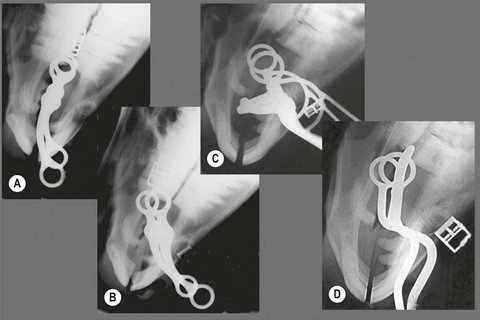

image

Fig. 3.8 Three types of gag bits. (A, B) Basic gag bit, in this example with a link in the mouthpiece. (C, D) Gag snaffle with half-O-rings. (E, F) Gag with full rings for attachment of snaffle rein.

Fig. 3.9 Radiographs of gag bits. (A) Ventrodorsal with no rein pressure. (B) Ventrodorsal under rein pressure. (C) Lateral with no rein pressure. (D) Lateral under rein pressure.

It might be thought that the gag functions to lower the head because tension on the reins places pressure on the poll. But head carriage is more a factor of where the horse finds relief from bit pressure. Since the horse’s mouth is much more sensitive to pressure than his poll, if the gag is used with no auxiliary aids, its net effect is to accentuate the basic head-raising action of a snaffle bit.8 If strong rein pressure is applied to a gag bridle, the bit is pulled relatively far caudally and can severely punish the horse’s tongue, lips and cheeks (Fig. 3.9).